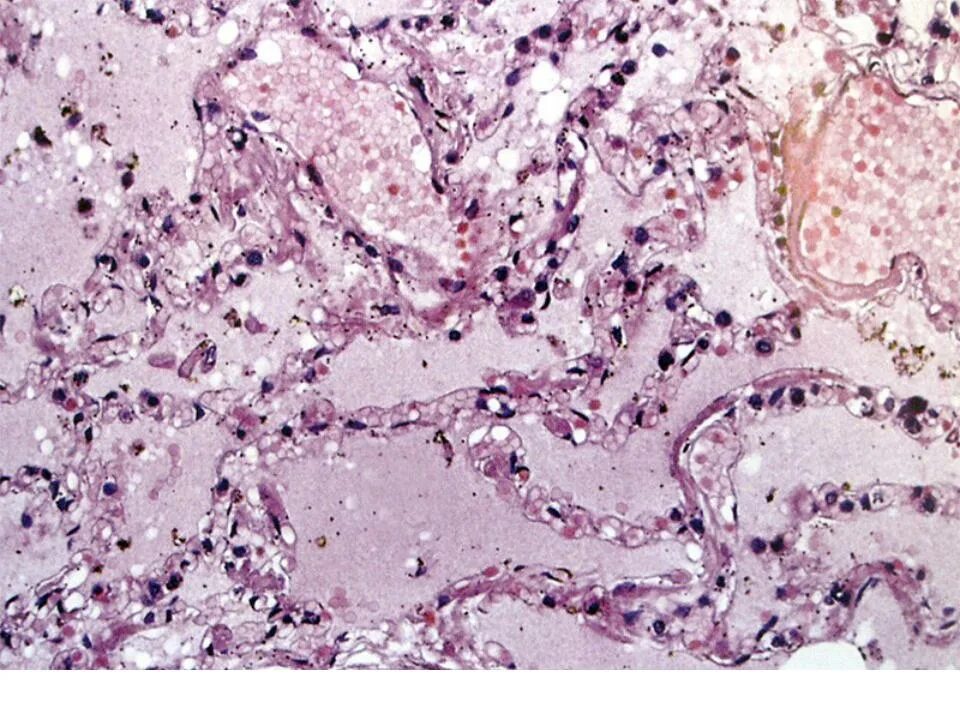

Атеросклеротический кардиосклероз 125.1